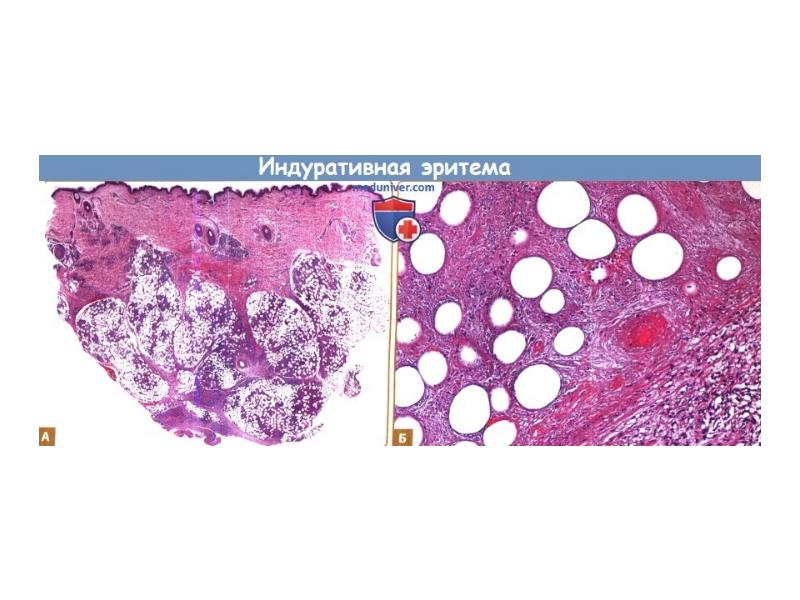

- 22. Индуративті эритема Индуративная эритема Базена – очаговое кожное заболевание, развивающееся на фоне

- 23. Индуративті эритема

- 24. Гистопатология индуративной эритемы Базена: - Преимущественно лобулярный или смешанный лобулярно-септальный панникулит